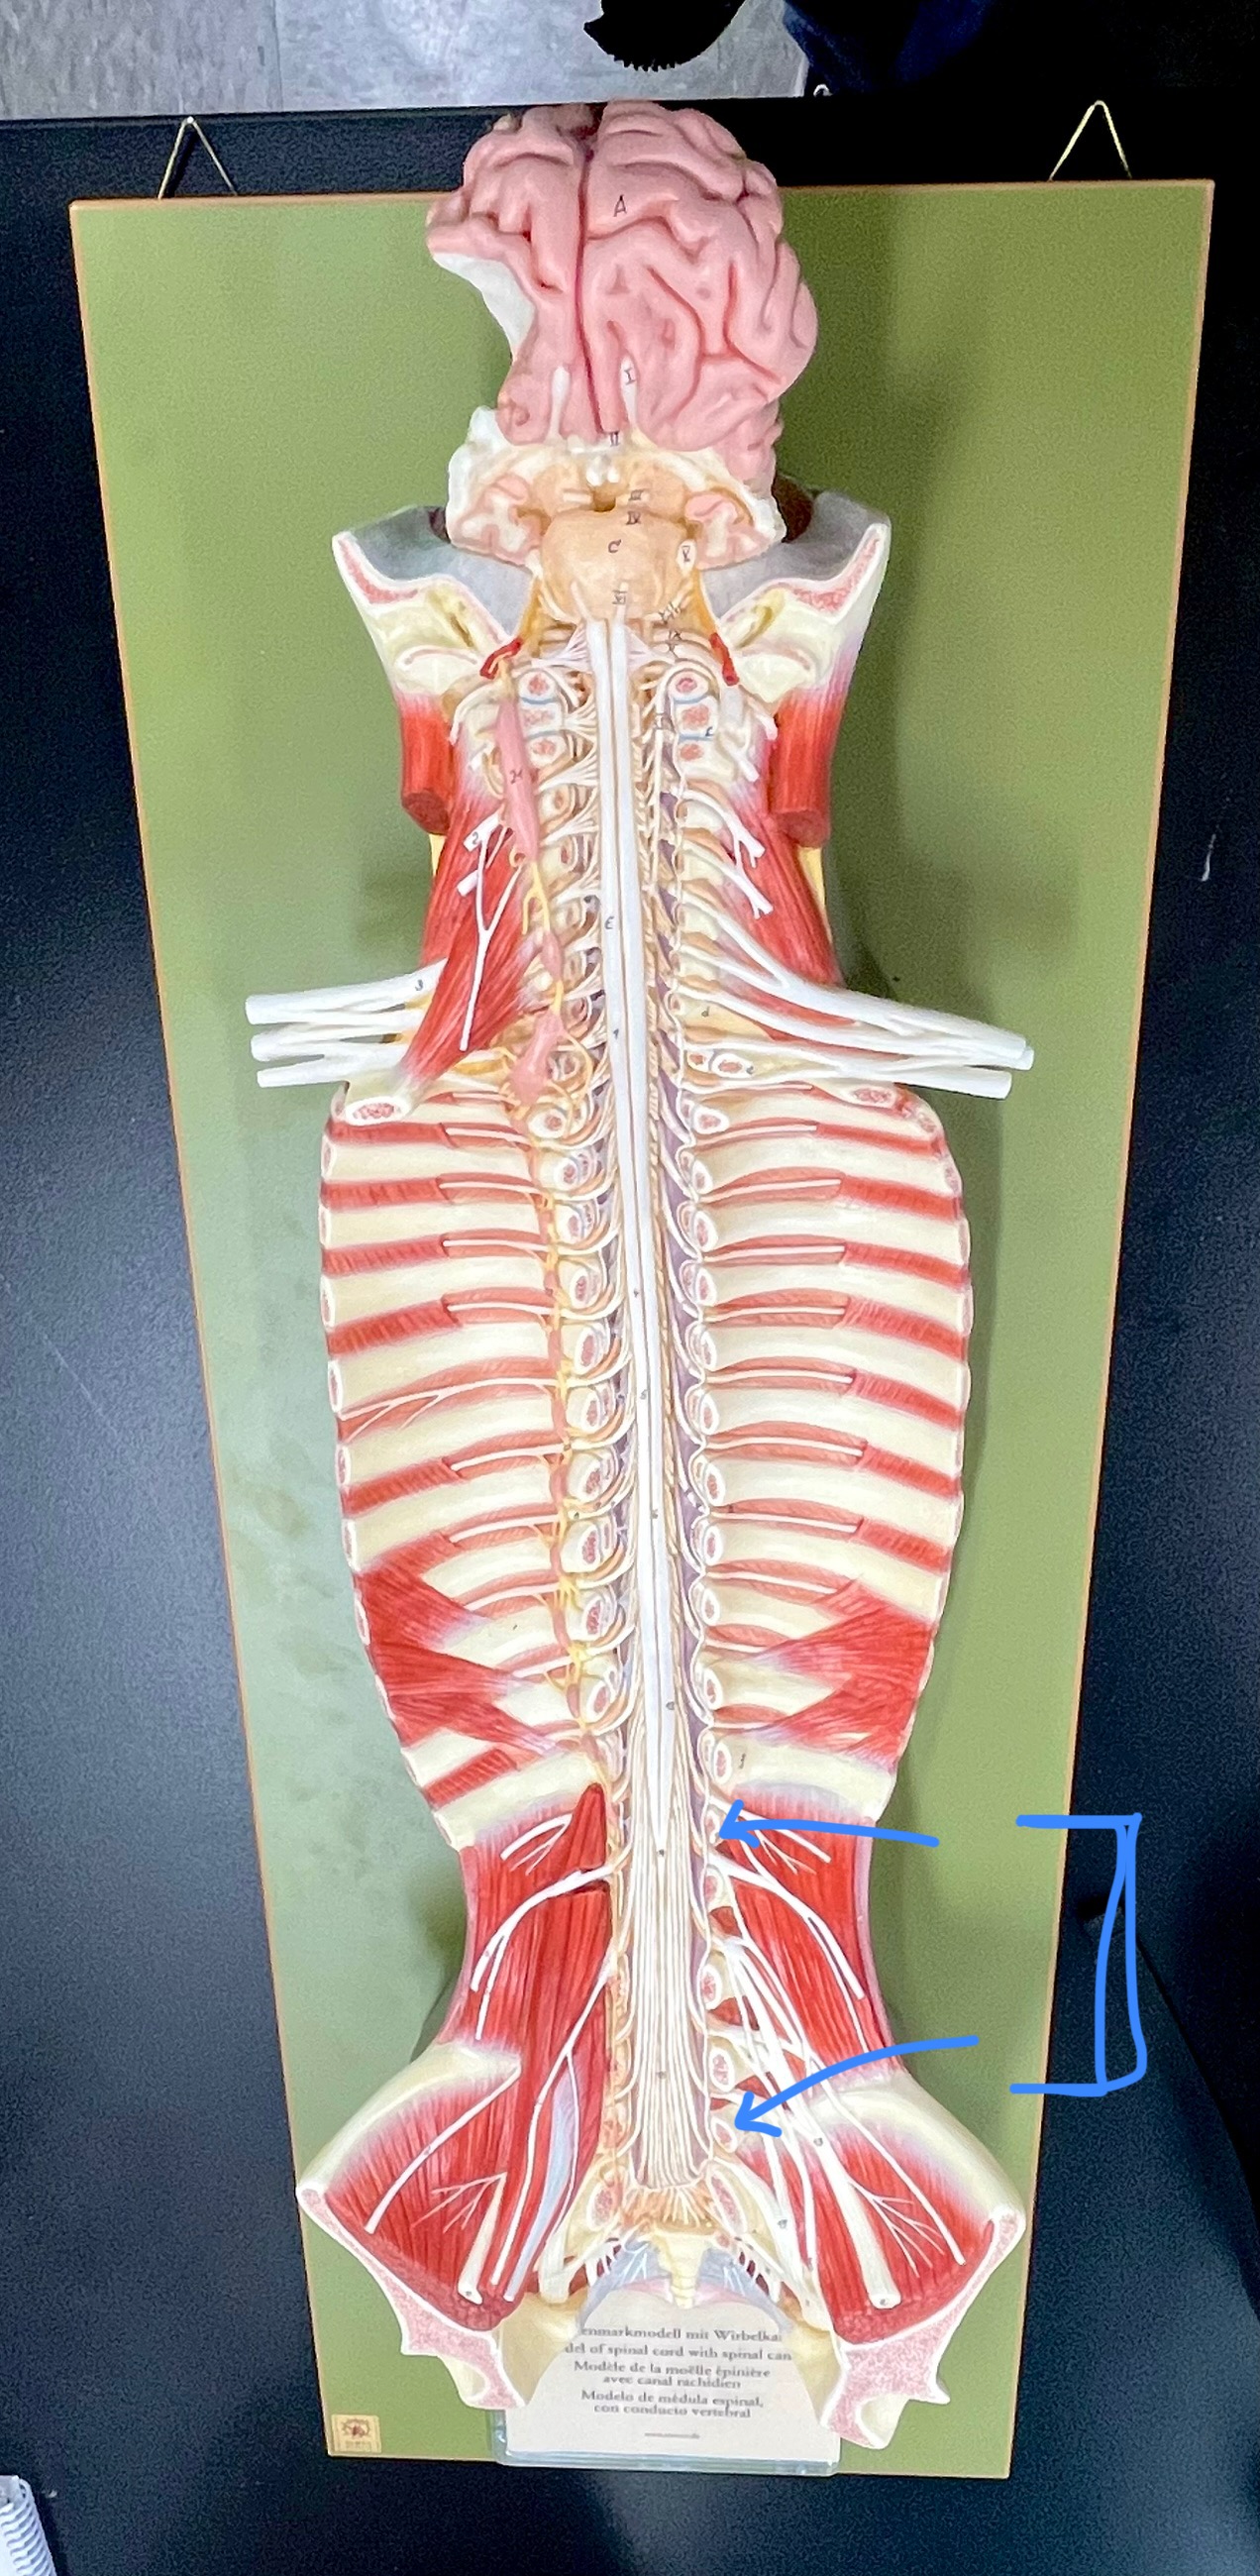

conus medullaris

conus medullaris

filum terminale

cauda equina

lumbar plexus – femoral nerve

lumbar plexus - femoral nerve

sacral plexus – sciatic nerve

sacral plexus – sciatic nerve